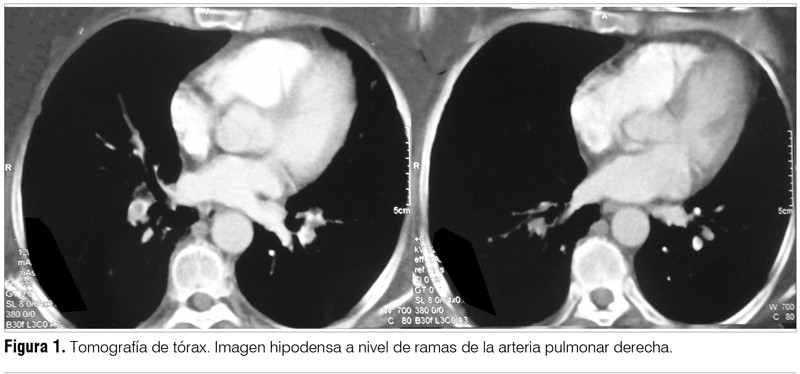

Establecido el diagnóstico de dicha enfermedad autoinmune, se realizó valoración en búsqueda de proceso neoplásico oculto sin evidencia del mismo. De la tomografía de tórax realizada por dicho motivo se destaca como hallazgo la presencia de un tromboembolismo pulmonar (TEP) (figura 1). Dado el hallazgo, se inició anticoagulación.